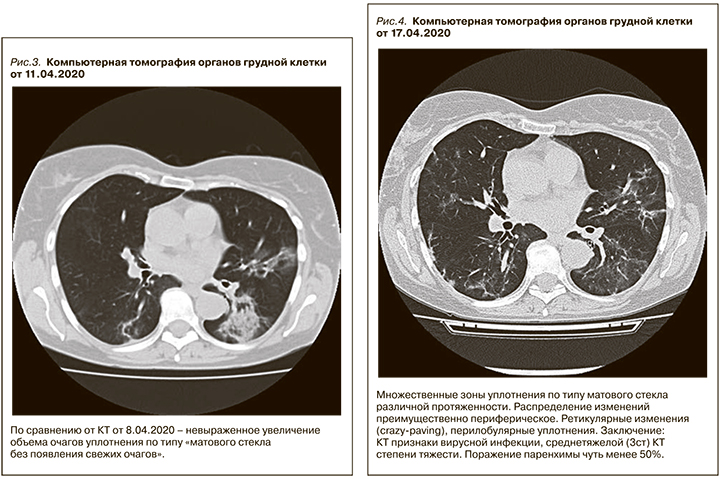

Настоящая госпитализация с 8 по 20 апреля 2020 г. Состояние при поступлении средней тяжести: одышки в покое нет, в легких дыхание везикулярное, в нижних отделах влажные мелкопузырчатые хрипы, синусовая тахикардия – 118 в мин. Умеренный лейкоцитоз (11х109 /л), СРБ – 116 мг/мл, креатинин в плазме крови – 140 мкмоль/л. По данным КТ органов грудной клетки, картина массивного двустороннего поражения легких, типичная для тяжелого COVID-19 (рис. 1).

На фоне вышеуказанной терапии развилась дисфункция трансплантированной почки, сохранялась выраженная лихорадка, прогрессировала лейкопения/лимфопения, значительно выросла концентрация такролимуса в крови, несмотря на значительное снижение дозы такролимуса – более чем в 3 раза, наросла концентрация С-реактивного белка. Зарегистрирована отрицательная динамика при компьютерной томографии органов грудной клетки (рис. 3 и 4) Отмечено прогрессирующее снижение SpO2 c 97 до 86%, несмотря на высокопоточную оксигенотерапию, антибактериальную и антикоагулянтную терапию